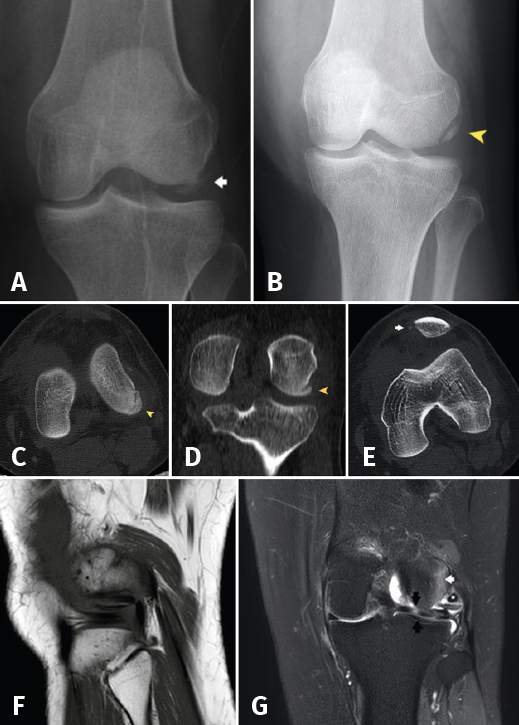

The initial radiographs revealed fracture of the external femoral condyle with an osteochondral fragment lodged in the lateral femorotibial joint space (Figure 1A). This displacement was not confirmed at radiological controls following immobilization (Figure 1B). Computed axial tomography (CAT) revealed a non-displaced double fracture line at the posterior margin of the external femoral condyle, parallel to the joint surface of the latter and measuring 21 mm in length, together with signs of avulsion fracture at the medial margin of the patella, with lateral subluxation (Figure 1B).

Figure 1. A: anteroposterior radiograph of the left knee. Osteochondral fragment of the external femoral condyle (arrow); B: reduced fragment in the initial anterosuperior radiograph (arrowhead); C: axial view; and D: coronal view of the initial CAT scan showing the osteochondral fracture without displacement (arrowhead); E: CAT coronal view showing fracture avulsion at the medial margin of the patella, with lateral patellar subluxation due to involvement of the medial retinaculum (arrow); F: MRI sagittal view showing the fragment and tendon of the TP; G: MRI coronal view showing bone edema of the external femoral condyle (white arrow) and subluxation of the TP (asterisk), together with horizontalization of the osteochondral fragment and a hyperintense image corresponding to rupture in the external meniscus with a pseudodiscoid appearance (black arrows).

At reassessment after 12 weeks, the patient reported "joint laxity" and "failing" of the knee. The physical examination revealed altered gait with great patient apprehensiveness and a tendency towards a "varus drive" pattern, overjet in the lateral femorotibial compartment with mild laxity +/+++ in varus and 0 and 30 degrees of flexion, together with an inconclusive dial test. The Lachman and anterior and posterior drawer in neutral rotation manoeuvres proved negative. The posterolateral rotary drawer test showed subtle asymmetry, with a joint balance of 0 at 115 degrees. The MRI study revealed a subchondral lesion in the loading zone of the external femoral condyle accompanied by intense bone edema and joint effusion. The external meniscus presented a pseudo-discoid appearance with suspected rupture (Figure 1C-D).